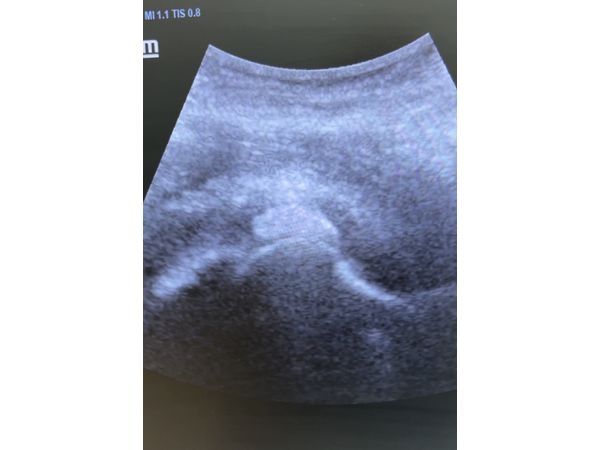

На УЗИ в области тазобедренного сустава диагностировали образование с однородным содержимым.

На УЗИ образований в проекции тазобедренного сустава не было. Пациентка стала нормально спать, ходит самостоятельно без дополнительной опоры, движения в полном объёме.